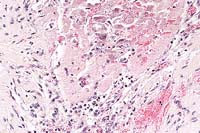

Case 23-3. Small colon. Mesenteric side showing a somewhat thin muscular layer (hypoplasia) and lack of of the submucosal and myenteric plexuses (no ganglion cells). 2X

Contributor's Diagnosis and Comments: Large and small colon: diffuse colonic hypoplasia and aganglionosis with meconium impaction. (Lethal white overo trait).

Submitted tissues include longitudinal sections of portions of the large colons and a transverse section of the small colon. Subgross examination of sections of small colon reveal the extremely small diameter of this filly's colon. The small size may be due to hypoplasia. Within the muscularis, myenteric ganglia are severely reduced in number although occasional nerve fibers can be identified.

1. Colon: Aganglionosis, diffuse, Paint, equine.

2. Colon: Hypoplasia, moderate.